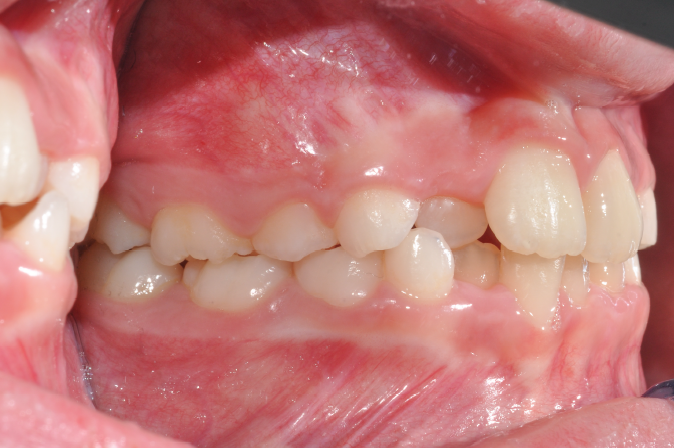

The patient presented with a skeletal Class I relationship and a mesofacial growth pattern, indicating balanced sagittal and vertical skeletal proportions. Dental examination revealed a Class I molar and canine relationship bilaterally. The patient was in the mixed dentition phase. Significant dental crowding was observed in both arches, consistent with a dentoalveolar discrepancy. Midline deviations were present, affecting dental symmetry and occlusal harmony. The maxillary lateral incisors were in crossbite, contributing to anterior transverse discrepancy and functional imbalance.

Periodontal evaluation revealed early signs of periodontal disease, primarily affecting tooth 41. Radiographic assessment demonstrated root convergence of teeth 11 and 21, indicating compromised root parallelism. Overall, the initial presentation was characterized by dentoalveolar crowding, transverse discrepancies, occlusal asymmetries, and early periodontal involvement within an otherwise favorable skeletal framework, requiring a carefully planned orthodontic approach to ensure functional stability and periodontal preservation.